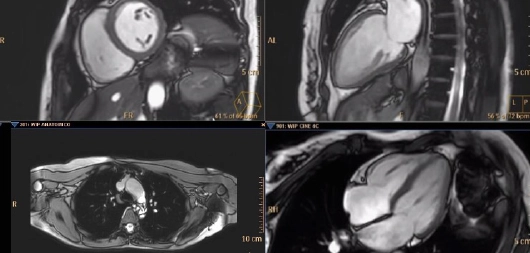

Figure 6

Different planes of a cardiac magnetic resonance scan